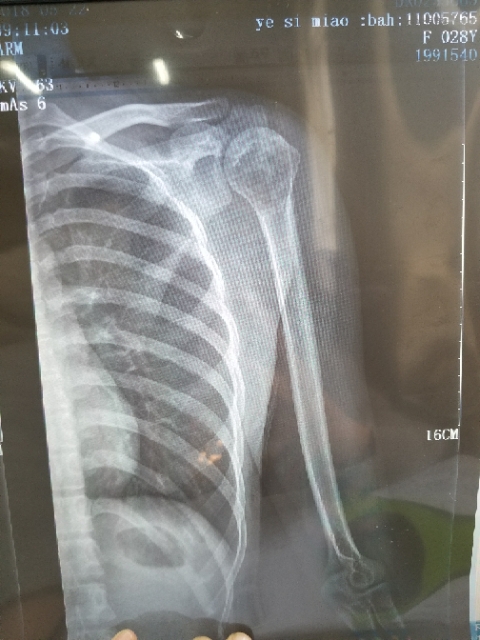

一路向北 02019-01-28 患者家属我孩子今年15岁,年初查出骨肉瘤,左腿关节处,化疗5次做载肢,手术后伤口感染误了化疗,两个多月快三个月发生肺转,如今刚住...